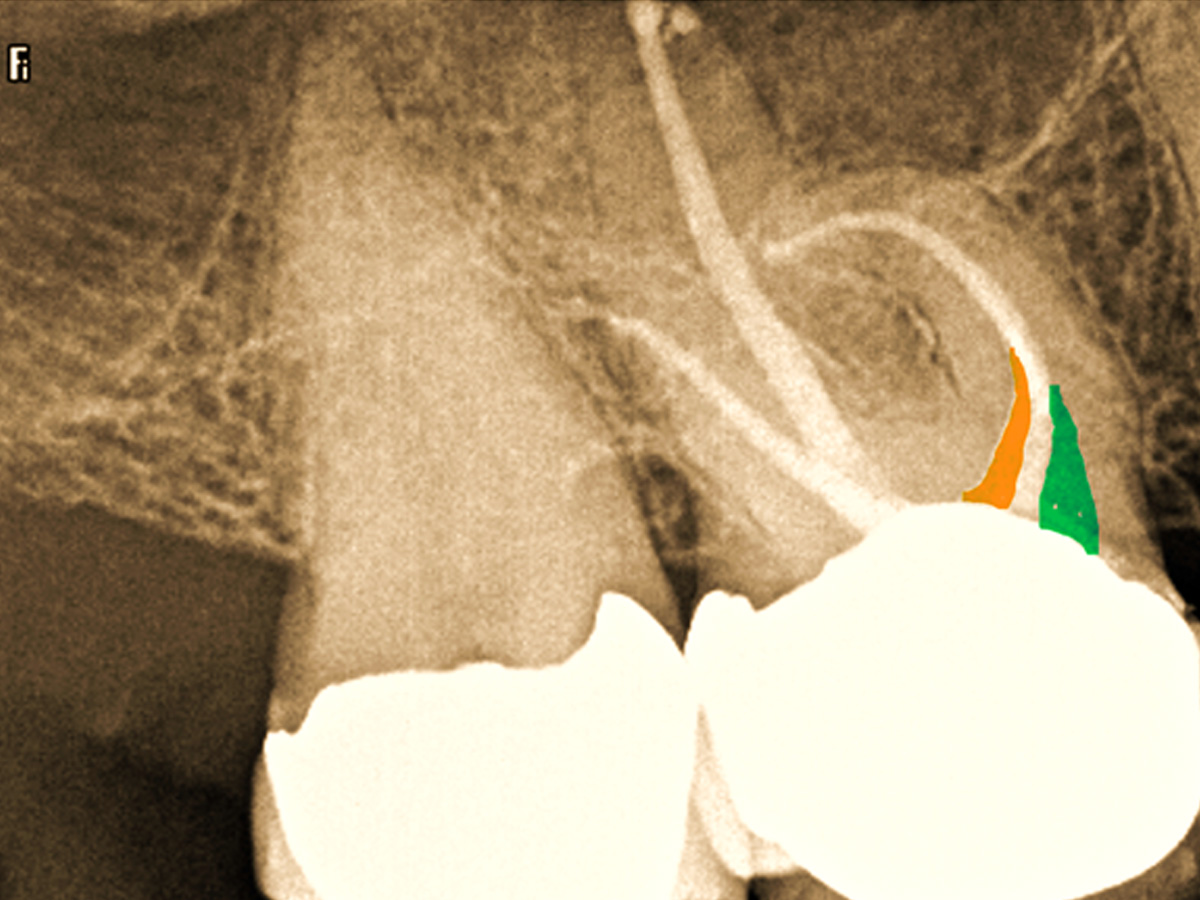

Abbildung 4

Die klassische Aufbereitung bei gekrümmten Kanälen erfolgt durch Erweiterung des Kanaleingangs mit konventionellen Stahlbohrern (Gates Glidden) oder NiTi Introfeilen mit höherer Konizität, was zu einer unnötigen Entfernung von Dentin am Kanaleingang führt (oranger Bereich). Um diese zu vermeiden wurden die Kanäle mit wärmebehandelten Niti-Feilen der neuesten Generation (FKG RACE EVO) bei 1.000 rmp/ 1,5 N-cm aufbereitet.

Abbildung 5

Der maschinelle Gleitpfad wurde mit der RACE EVO 15.04 geschaffen und die Kanäle bukkal bis 35.04 und palatinal bis 50.04 präpariert.

Abbildung 7

Im koronalen Drittel wurden eine schonende Dentinabtragung (grüner Bereich) und Zugang zum Kanal durchgeführt. MB2 (oranger Bereich).